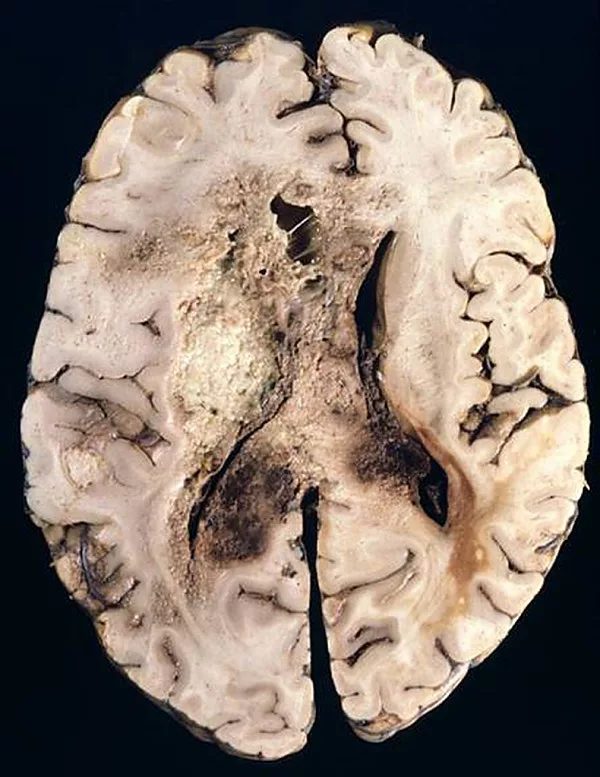

Болезнь Крейтцфельтда-Якоба

1 место среди смертельных инфекций досталось губчатой энцефалопатии, она же болезнь Крейтцфельда-Якоба. Инфекционный агент-возбудитель обнаружен сравнительно недавно – с прионными заболеваниями человечество познакомилось в середине ХХ века. Прионы – белки, вызывающие нарушение функций, а затем и гибель клеток. Из-за особой устойчивости могут передаваться от животного к человеку через пищеварительный тракт – человек заболевает, съев кусок говядины с нервной тканью зараженной коровы. Болезнь дремлет годами. Затем у пациента начинают нарастать расстройства личности – он становится неаккуратным, сварливым, впадает в депрессию, страдает память, иногда – зрение, вплоть до слепоты. За 8-24 месяца развивается деменция (слабоумие), больной погибает от нарушений мозговой деятельности. Заболевание очень редкое (за последние 15 лет заболело всего 100 человек), но абсолютно неизлечимое.